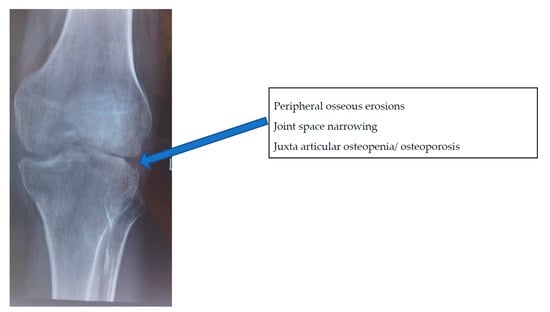

- Stage of early arthritis. Patient presents with joint pain, spasm of the surrounding muscle, and difficulty in doing some activities of daily living. Affected joint has 50–75% of the joint movement preserved. X-ray shows classical Phemister’s triad of juxta-articular osteopenia, mild joint space reduction, and peripheral osseous erosions. This stage has good prognosis with mild stiffness.

2.2. Imaging Features